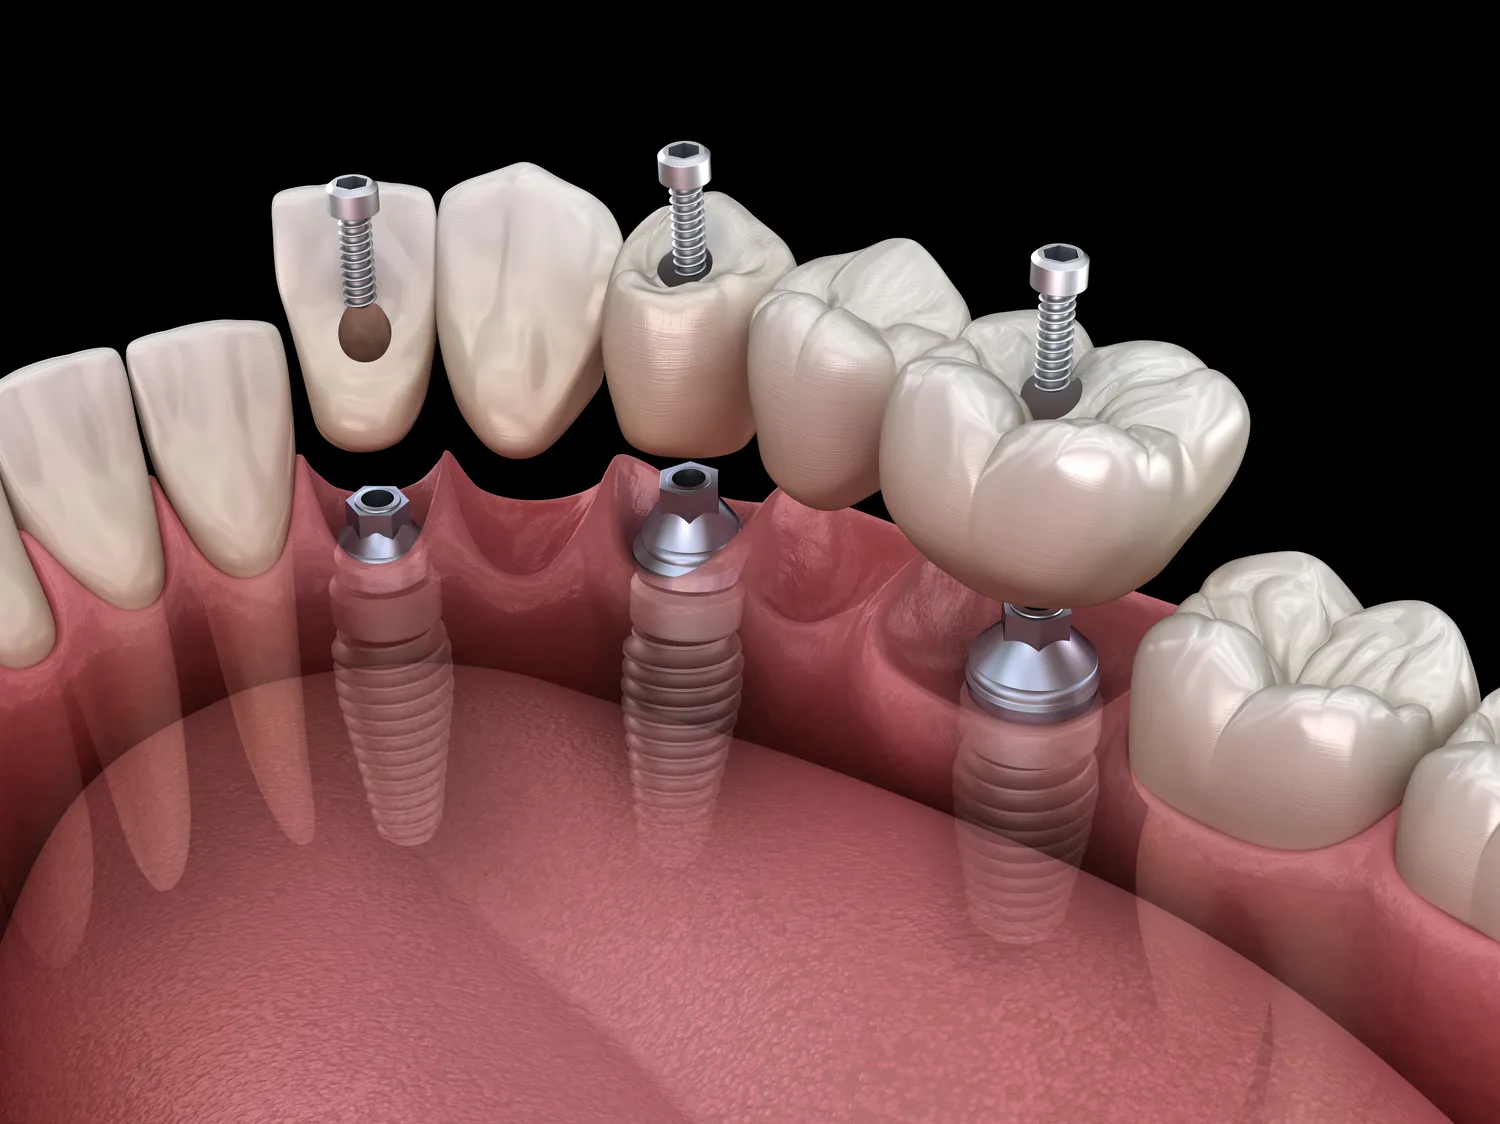

W ramach różnych specjalności stomatologicznych wykonywane są liczne zabiegi, które mają na celu poprawę zdrowia jamy ustnej oraz estetyki uśmiechu. Stomatolog ogólny przeprowadza podstawowe procedury, takie jak wypełnianie ubytków, leczenie kanałowe czy usuwanie zębów. W przypadku bardziej skomplikowanych problemów pacjenci mogą być kierowani do specjalistów, takich jak ortodonta czy periodontolog. Ortodonta wykonuje zabiegi związane z korekcją wad zgryzu poprzez zakładanie aparatów ortodontycznych oraz monitorowanie postępów leczenia. Z kolei periodontolog podejmuje działania w zakresie diagnostyki i terapii chorób dziąseł oraz tkanek otaczających zęby. W ramach chirurgii stomatologicznej przeprowadzane są operacje wymagające interwencji chirurgicznej, takie jak implantacja zębów czy rekonstrukcja kości szczękowej. Dodatkowo stomatolodzy często oferują usługi związane z estetyką uśmiechu, takie jak wybielanie zębów czy zakładanie licówek porcelanowych.

Stomatologia estetyczna to dziedzina, która dynamicznie się rozwija i wprowadza nowoczesne rozwiązania mające na celu poprawę wyglądu uśmiechu pacjentów. Jednym z najnowszych trendów jest stosowanie licówek porcelanowych, które pozwalają na korekcję kształtu i koloru zębów bez konieczności ich szlifowania. Licówki są cienkimi nakładkami wykonanymi z wysokiej jakości materiałów ceramicznych, które idealnie imitują naturalny wygląd zębów. Innym popularnym zabiegiem jest wybielanie zębów, które można przeprowadzać zarówno w gabinecie stomatologicznym, jak i w warunkach domowych przy użyciu specjalnych zestawów. W ostatnich latach coraz większą popularnością cieszą się również implanty dentystyczne jako trwałe rozwiązanie dla osób z brakami w uzębieniu. Implanty są wszczepiane w kość szczękową i stanowią solidną podstawę dla koron lub protez. Coraz częściej stosuje się także techniki minimalnie inwazyjne, takie jak laseroterapia czy bonding kompozytowy, które pozwalają na przeprowadzanie zabiegów bez konieczności stosowania narkozy czy długiego okresu rekonwalescencji.

Koszty usług stomatologicznych mogą się znacznie różnić w zależności od rodzaju zabiegu oraz specjalizacji lekarza. W przypadku stomatologii ogólnej ceny za standardowe procedury takie jak przegląd dentystyczny czy leczenie próchnicy wahają się od kilkudziesięciu do kilkuset złotych. Koszt bardziej zaawansowanych zabiegów, takich jak leczenie kanałowe czy ekstrakcja zęba mądrości, może wynosić od kilku setek do nawet kilku tysięcy złotych w zależności od stopnia skomplikowania przypadku oraz lokalizacji gabinetu dentystycznego. W przypadku ortodoncji ceny aparatów ortodontycznych mogą zaczynać się od około dwóch tysięcy złotych za aparat stały i sięgać nawet dziesięciu tysięcy złotych za bardziej skomplikowane przypadki wymagające długotrwałego leczenia. Koszt implantacji zębów również jest znaczny – ceny wahają się od kilku do kilkunastu tysięcy złotych za jeden implant wraz z koroną protetyczną. Warto również zwrócić uwagę na to, że wiele gabinetów oferuje różne formy finansowania usług dentystycznych oraz programy lojalnościowe dla pacjentów regularnie korzystających z ich usług.